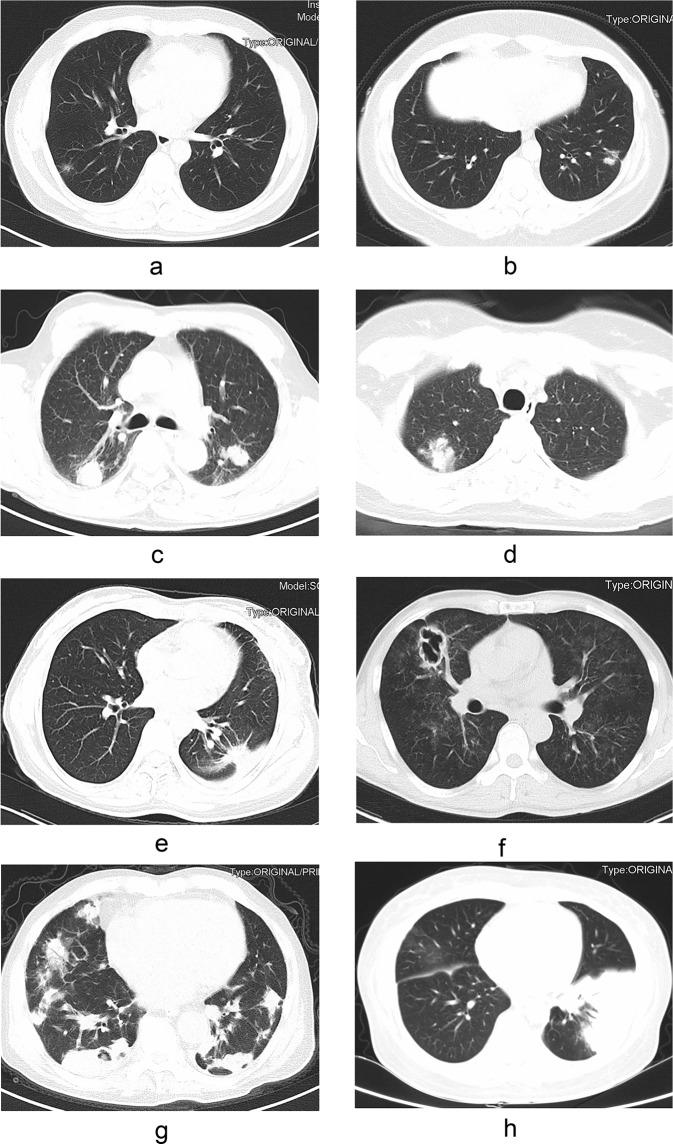

Cryptococcosis is a systemic infection and it may occur in immunocompromised and immunocompetent hosts. In order to better understand the clinical characteristics of patients with PC in different immune status, we retrospectively investigated the clinical, radiological, and treatment profiles of immunocompetent and immunocompromised patients with PC during a 10-year period (2008-2017). As a result, out of 136 patients, 94 (69.1%) were immunocompromised hosts. For the PC patients without CNS involvement, higher percentage of immunocompetent patients (39.5%, 15/38) had asymptomatic presentation than immunocompromised patients (6.3%, 3/48) (P < 0.05). Multiple pulmonary nodules (72.7%, 56/77), ground-glass attenuation/interstitial changes (94.4%, 17/18) and cavitation (88.6%, 31/35) were significantly frequent in immunocompromised patients (P < 0.05). A total of 47 patients were misdiagnosed as tuberculosis or tumors based on CT signs. PC was likely to be misdiagnosed as tuberculosis in immunocompromised patients (88.2%, 15/17), and tumor was more likely to be considered in immunocompetent patients (43.3%, 13/30). Immunocompetent patients accounted for 80% (24/30) of patients with definite diagnosis on surgical lung biopsy. Fluconazole monotherapy can achieve good clinical outcome in most PC patients without central nervous system (CNS) involvement (91.5%, 54/59). After 3 months of treatment, 92.7% (38/41) patients have improved imaging findings. In conclusion, PC has diverse imaging manifestations and it is easily misdiagnosed. Lobectomy should be carefully selected in immunocompetent patients with a single lung lesion. Fluconazole monotherapy is preferred for PC patients without CNS involvement.